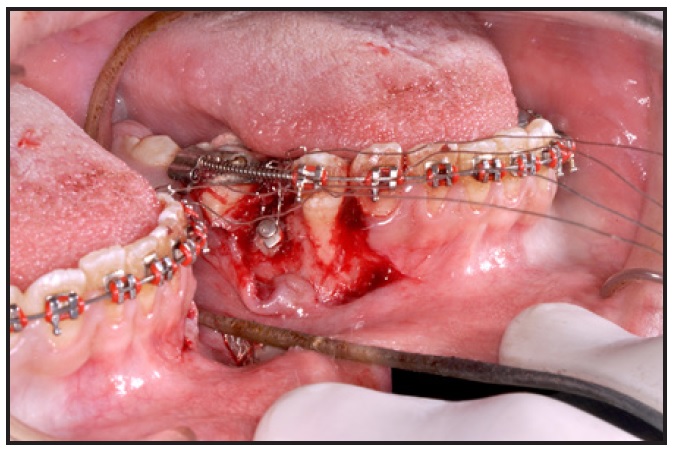

The palatally impacted upper right canine was surgically exposed with a palatal flap. A button was bonded to its lingual surface, and a ligature wire was wrapped around the button head to act as a means of attachment after flap closure (Fig. 3).

Fig. 3 Surgical exposure of palatally impacted upper right canine.